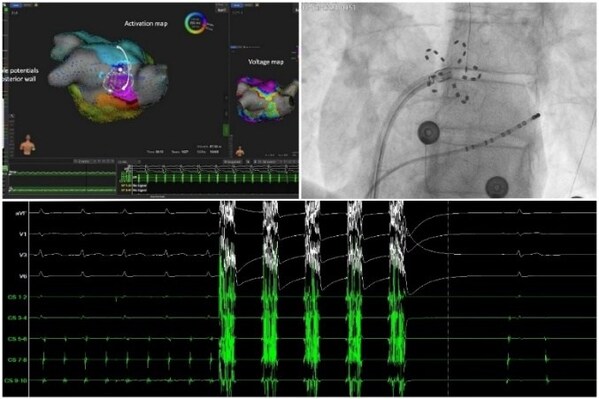

FARAPULSE脉冲电场消融新技术手术